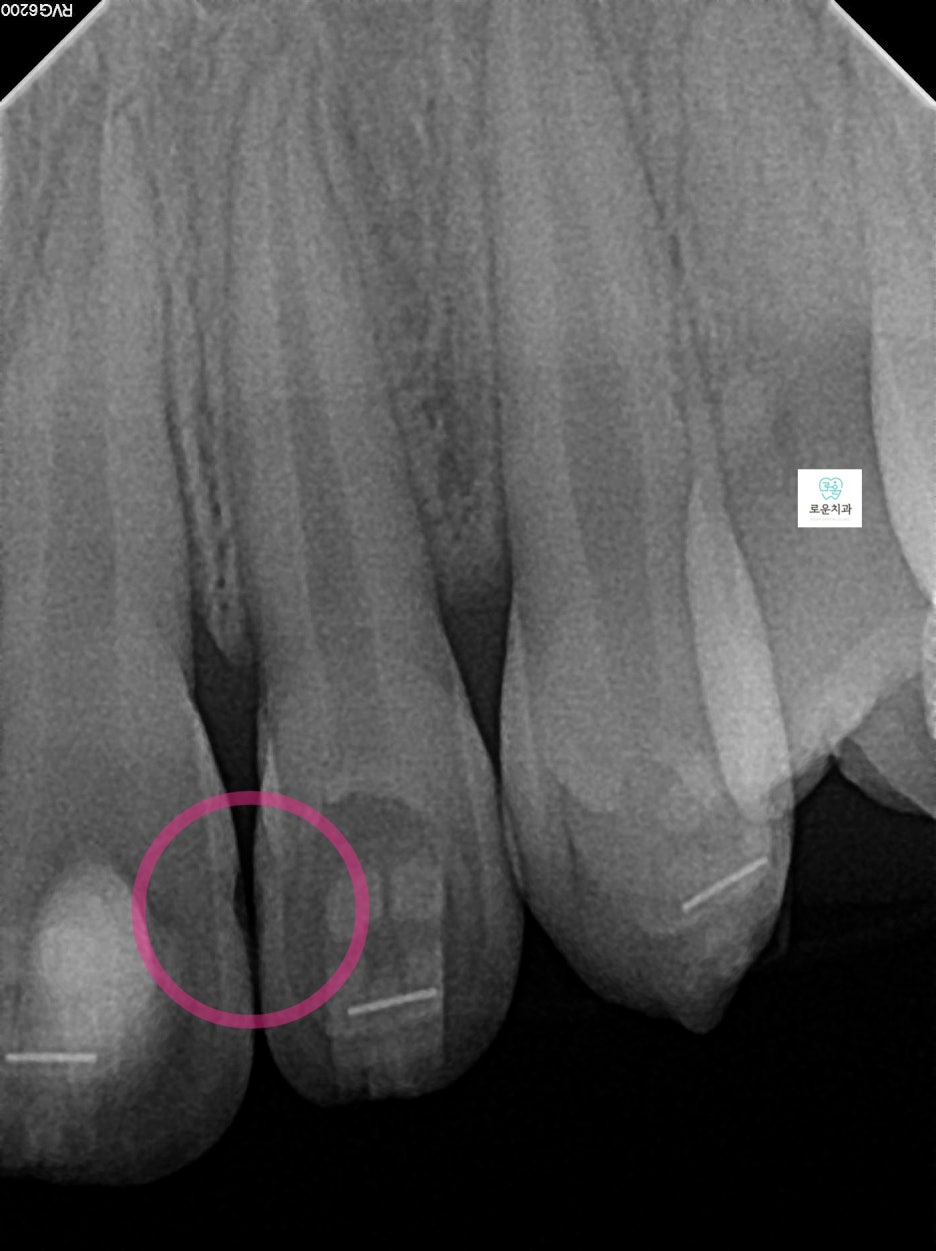

엑스레이 촬영 결과

인접면 충치가 더욱 명확하게 확인되었으며

깊이에 따라 마취 후 치료를 진행했습니다.

앞니에 생긴 우식은 치아 4개에 사이에 생겨 총 6면의 우식이 발생

→ 치아는 붙어 있는 면 양쪽으로 우식 진행되기 때문에 면수로 진행